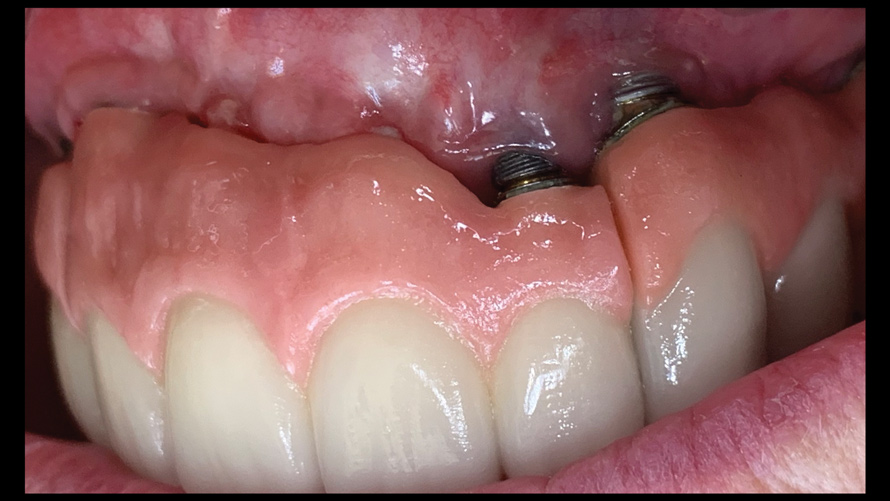

(16.) Photograph of failing implant prosthetics that may require specialty care taken with a smartphone and an EALS device.

Figure 16

(17.) Photograph of failing implant prosthetics that may require specialty care taken with a smartphone and an EALS device.

Figure 17